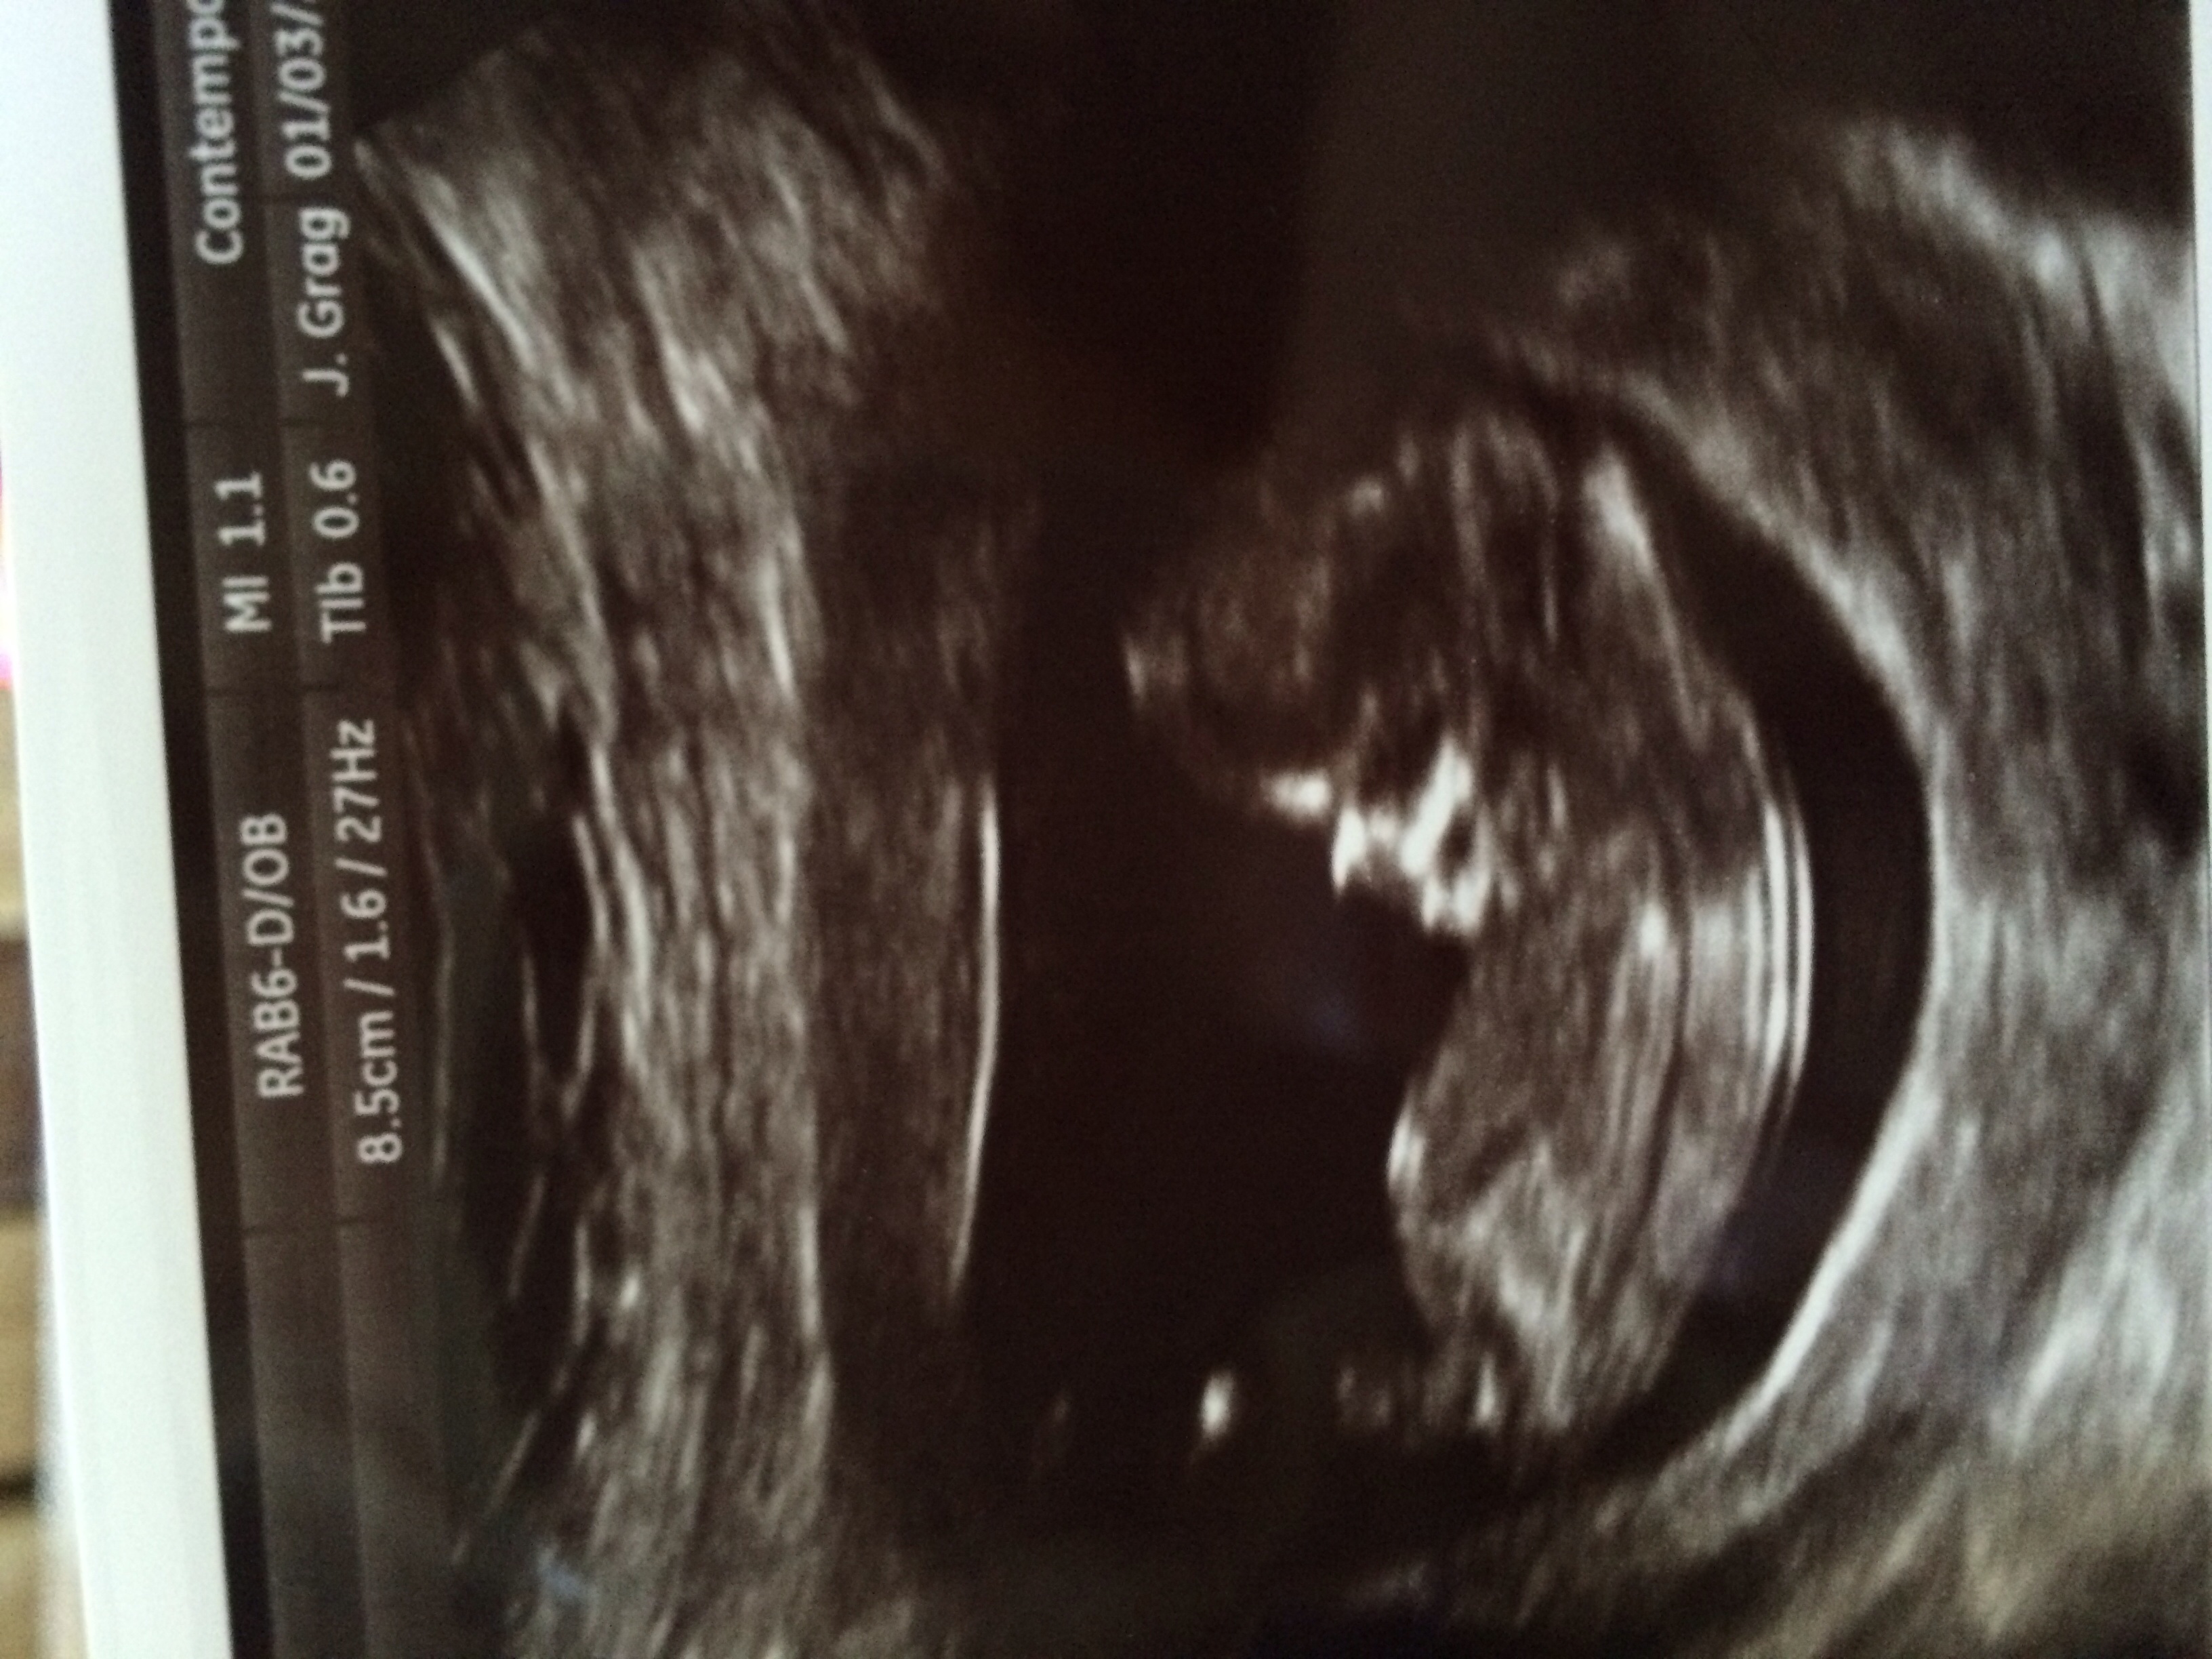

Any guess on nub??

If the nub is where the arrow is, I'd guess girl. The angle is less than 30 degrees

The end goes up a bit. But not enough to make me think boy, Ill guess girl :)

Nervous it will rise being it was only 12 weeks? Any input?

I'm with hotdogz, it isn't pointed down enough for me to say 100% girl. That said, it looks way more girl than boy. THAT said (lol)...was this taken in the beginning of the 12th week, or the very end? That makes a difference too. I am very cautious when nub-guessing for others b/c I had 50% girl guesses on my DS3's 12w5d nub shot, with one tech saying girl too. I had 100% girl guesses on his 11w5d nub shot (so close to 12 weeks). So like I said, I am very conservative when nub guessing. ;)